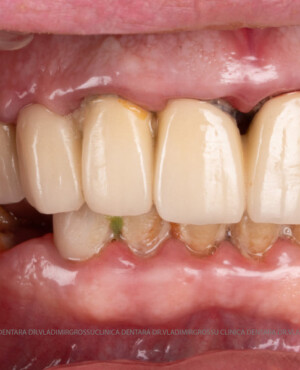

Caz 1